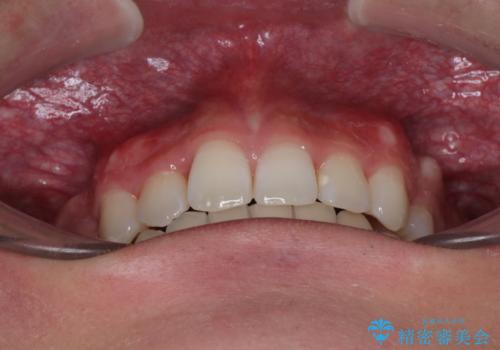

治療後には、デコボコと正中の位置が改善し、見た目だけでなく歯磨きがしやすい清潔なお口の環境を手に入れました。